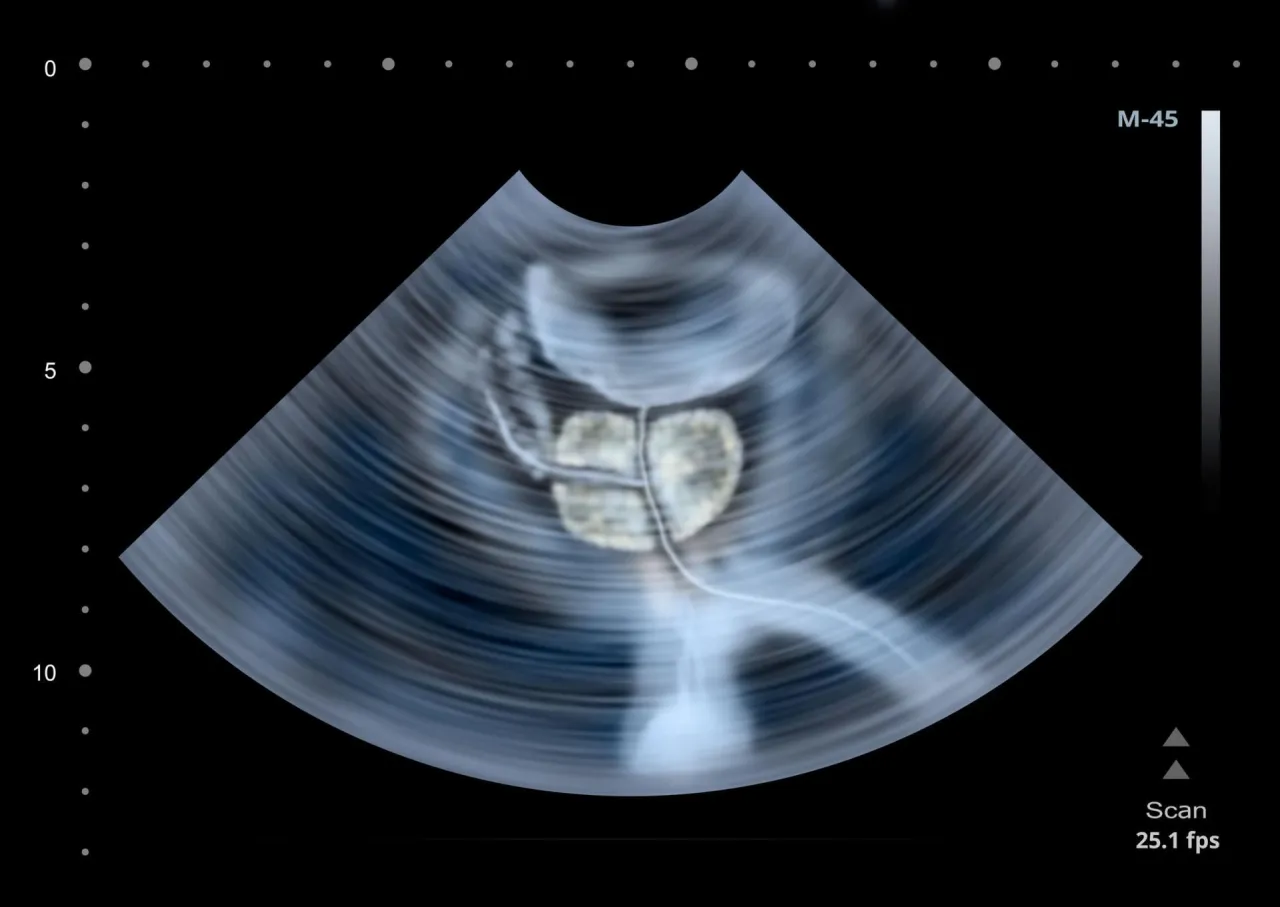

- USG układu moczowego: Szczegółowe badanie nerek, pęcherza moczowego, a u mężczyzn również prostaty.

- TRUS (USG przezodbytnicze prostaty): Bardzo dokładne badanie prostaty, często wykonywane w celu oceny jej struktury i wykrycia zmian.